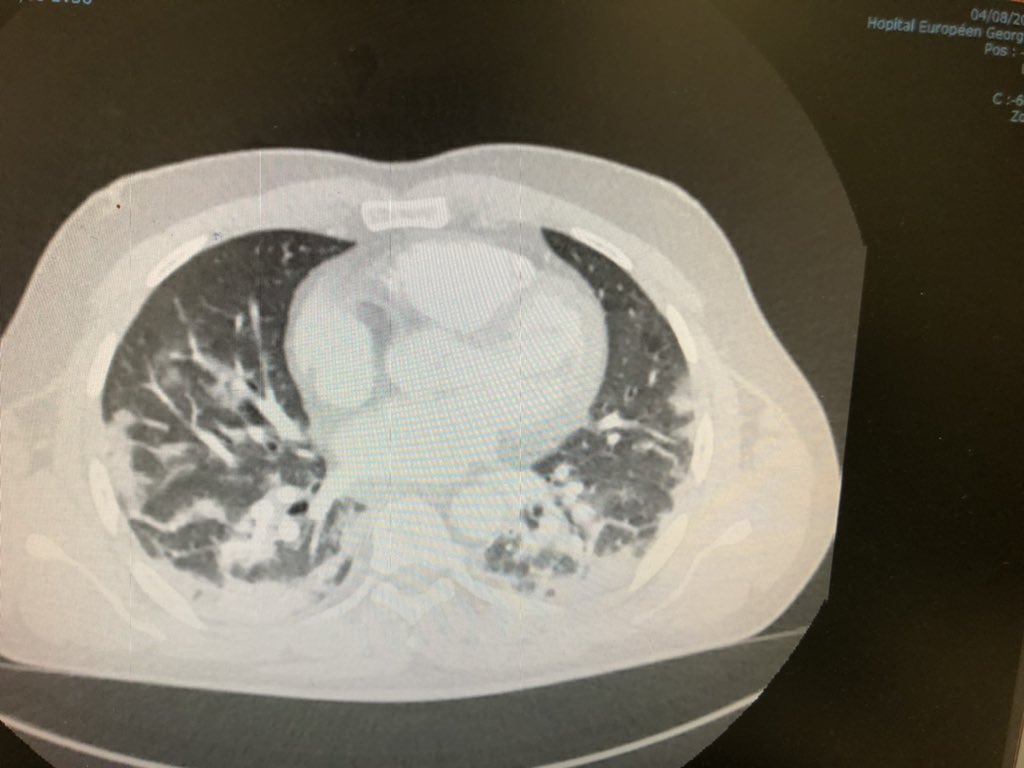

Ce matin. 42 ans. Pas vacciné. Le patient sous oxygène :"j'ai été bien con". Le scanner montre une atteinte à 50 % des poumons. Faites-vous vacciner.pic.twitter.com/ZHVrWDCq47